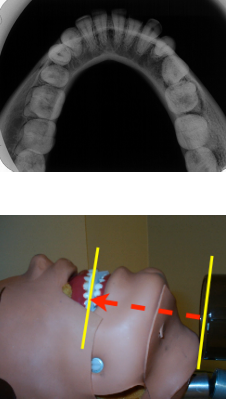

The bisecting angle technique is based on the geometric principle that states that two triangles are equal if they have two equal angles and a common side

This rule helps us determine the correct vertical angulation to us in order to get equal triangles on either side of the bisecting angle.

If the bisecting angle rule is neglected-(even slightly) the resulting radiographic image will be distorted.

If the vertical angulation of the BID is too large the image will be __________.

Foreshortened

If the vertical angulation of the BIDis too small the image will be __________

Elongated

What is the general verticle angulation that should be used for mx molars and premolars?

+20 to +30 degrees

What is the general verticle angulation for mandibular molars and premolars?

-20 to -30 degrees